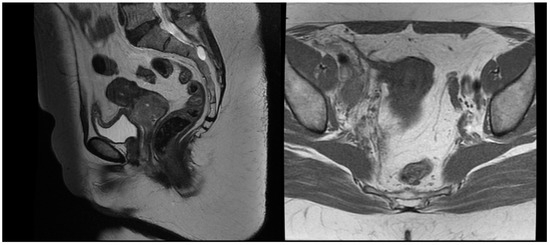

A 54-year-old woman presented in a gynecology department complaining of postmenopausal bleeding. She had been in amenorrhea for 2 years with no history of previous gynecological illness, one normal childbirth, and no family history of malignancies. She suffers from inherited recessive DEB, which was diagnosed at the age of 32. A biopsy of the uterine cervix revealed invasive squamous carcinoma G2. The patient was referred to the gynecological oncology clinic. Examination confirmed a cervical tumor with a size above 4 cm and no signs of parametrial invasion. MRT and PET/CT findings proved a tumor with an axial size of 46/32 mm and 34 mm craniocaudally with invasion of the vaginal vaults (Figure 1) and multiple bilateral pelvic lymph nodes involved, which were hypermetabolic with a highest SUV max of 42.6 (Figure 2). The stage of the disease was defined as cT2a2 cN1 M0, FIGO IIA. At the tumor board discussion, based on the current guidelines, definitive combined chemoradiotherapy was recommended. The patient presented herself at the radiation oncology department with complaints of intermittent pelvic pain, urinary stress incontinence, and occasional very mild vaginal bleeding. Dystrophic skin lesions were observed on the forearms, calves, and pubic area. Severe dystrophy of the nails was present. Recorded risk factors included obesity (body mass index 36.7) and tobacco smoking.

Figure 1.

T2 weighted MRT images before treatment.